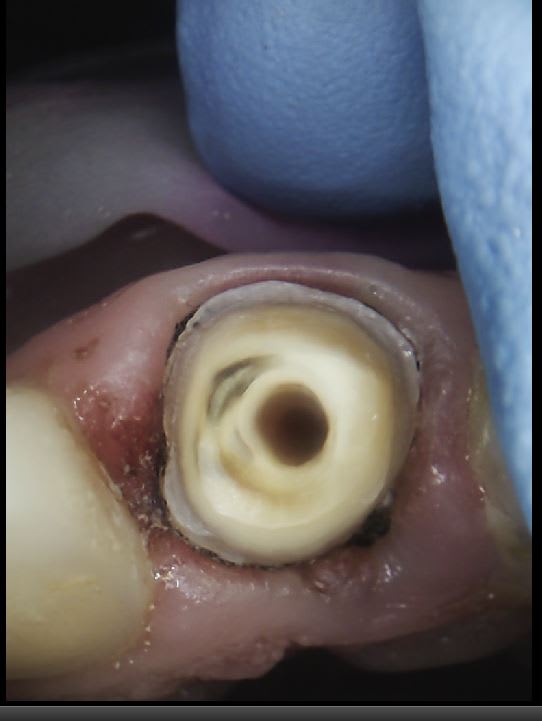

28/10/2021 à 13h19

enlaye, mon Maître, mon Roi, mon Idole....tu ne veux pas éponger avec une compresse avant de faire ta photo , les dentinoblastes ne t'en voudront pas trop et on verrait mieux l tes tailles d'anthologie?😘